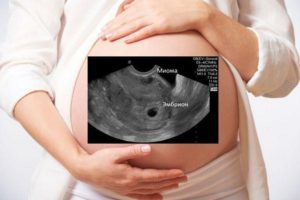

Можно ли перепутать миому с беременностью во время проведения ультразвуковой диагностики? Современные аппараты для УЗИ уменьшают такую вероятность практически до 0%.

Единственным вариантом, когда возможна такая путаница, является малый размер миомы, не превышающий плодное яйцо. Но буквально следующее проведенное УЗИ должно показать что находится в матке на самом деле.

Перепутать плодное яйцо на 5 неделе с миомой уже весьма затруднительно.

Гинеколог может заподозрить миому во время осмотра. Матка будет увеличена, как во время беременности. Это и служит источником опасений пациенток, что миому можно перепутать с беременностью.

Размер миомы принято считать в неделях беременности, поскольку раньше, без УЗИ-аппарата, невозможно было определить точный размер новообразований в сантиметрах.

Поэтому расчеты проводили, исходя из увеличения объемов детородного органа.

Современные методы исследований позволяют точно определить, что происходит в организме. Это исключает вероятность, что миому можно с чем-то перепутать. На УЗИ можно определенно точно увидеть характер образования, вычислить размеры и локализацию. Плодное яйцо будет сильно отличаться от миомы, поэтому спутать их нельзя.